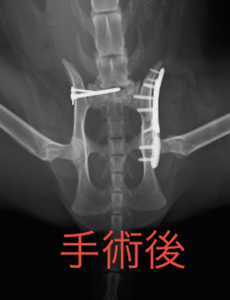

ある程度まで回復してくれたので、次はこの子に何が起こったのか、傷を追った原因は何かを調べていきました。すると、レントゲン検査で「骨盤骨折」と「仙腸関節脱臼」(骨盤の関節の脱臼)が見つかりました。

その後、整形外科の先生に骨折の手術をしてもらいお家の中で元気に過ごしています!